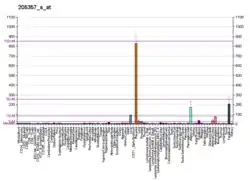

A huge number of polymorphisms is reported in the databases for AT1R which provide an avenue to explore these polymorphisms for their implications in protein structure, function and drug efficacy. Methods In the current study all the SNPs (10234) reported in NCBI were analyzed and SNPs which were important in protein structure and drug interactions were identified. Structures of these polymorphic forms were modeled and in silico drug interaction studies were carried out. Results Result of the interaction studies with polymorphism was in correlation with the reported case. Two SNP mutated structures of AT1R i.e. rs780860717 (G288T), rs868647200 (A182C) shows considerably less binding affinities in case of all angiotensin receptor blockers (ARBs).[14]